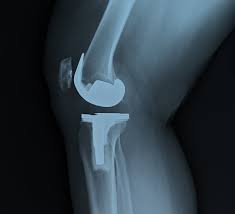

Accurate diagnosis forms the foundation of successful joint surgery. Therefore, doctors perform detailed physical examinations along with imaging studies such as X-rays and MRI scans. Moreover, assessments of joint alignment, ligament stability, and muscle strength guide surgical planning. In addition, surgeons design personalised treatment strategies based on joint anatomy and functional goals. Consequently, implant selection and alignment correction remain patient-specific rather than generic. This structured planning approach improves predictability and ensures that surgery directly addresses the underlying joint problem.

Modern joint surgery relies on refined surgical techniques that improve accuracy and joint function. Therefore, surgeons focus on precise bone preparation and balanced soft-tissue handling. Moreover, controlled surgical execution supports joint alignment and stability. In addition, standardised intraoperative protocols reduce variability and enhance safety. Consequently, patients benefit from improved joint mechanics and reliable outcomes. These techniques reflect ongoing advancements in orthopaedic surgery and reinforce confidence in approved surgical care.